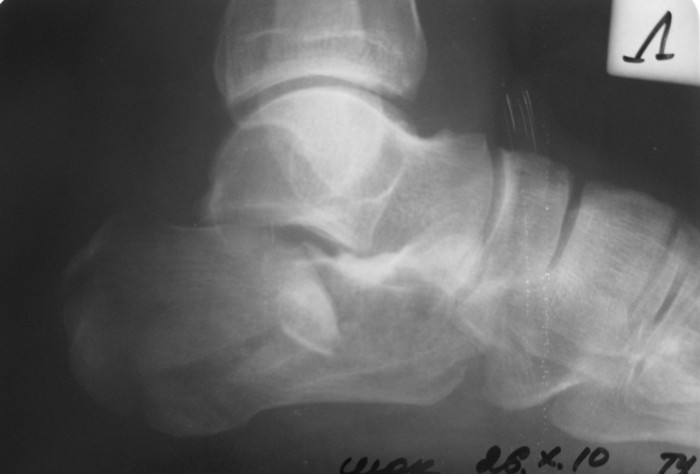

Мужчина, 47 лет. Диагноз: Кататравма (26.10.10г. падение с высоты 2го этажа).

Открытый оскольчатый внутрисуставной перелом дистального метаэпифиза лучевой кости, перелом шиловидного отростка локтевой кости левого предплечья со смещением отломков, закрытый оскольчатый внутрисуставной перелом дистального метаэпифиза лучевой кости, перелом шиловидного отростка локтевой кости правого предплечья со смещением отломков. Закрытый оскольчатый внутрисуставной перелом левой пяточной кости, закрытый оскольчатый внутрисуставной перелом дистального метаэпифиза обеих костей правой голени со смещением отломков, закрытый компрессионно-оскольчатый перелом тела L2 позвонка с болевым вертеброгенным синдромом.

Во время клинического разбора мнения разделились: 1) открытая репозиция, МОС пяточной пластиной 2) гипсовая иммобилизация 3) ЧКО аппаратом внешней фиксации как репозиционный и окончательный вариант остеосинтеза. 4) необходимость СКТ?

Коллеги, пожалуйста, интересует ваше мнение относительно тактики лечения, необходимого перечня рентгенологического обследования оскольчатого внутрисуставного перелома пяточной кости и сроков выполнения предполагаемой операции. Просим высказать мнение относительно необходимости выполнения СКТ как важного этапа диагностики.